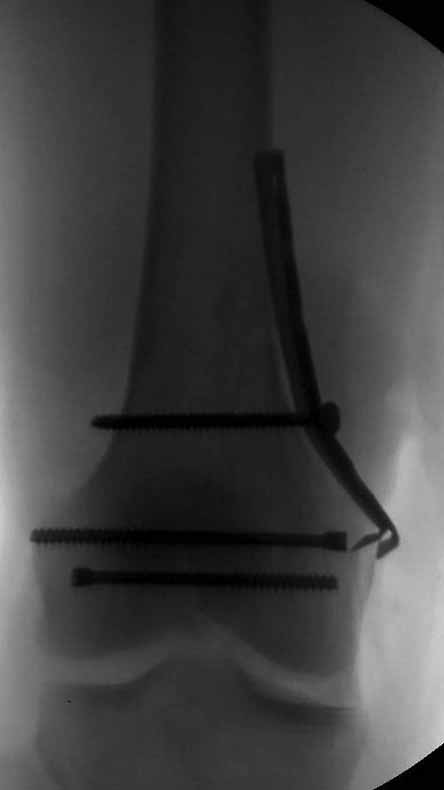

Здесь пример медиальной пластины и латеральный комбинированный метод (у второго больного старый перелом тибиал плато, леченный где то и когда то)